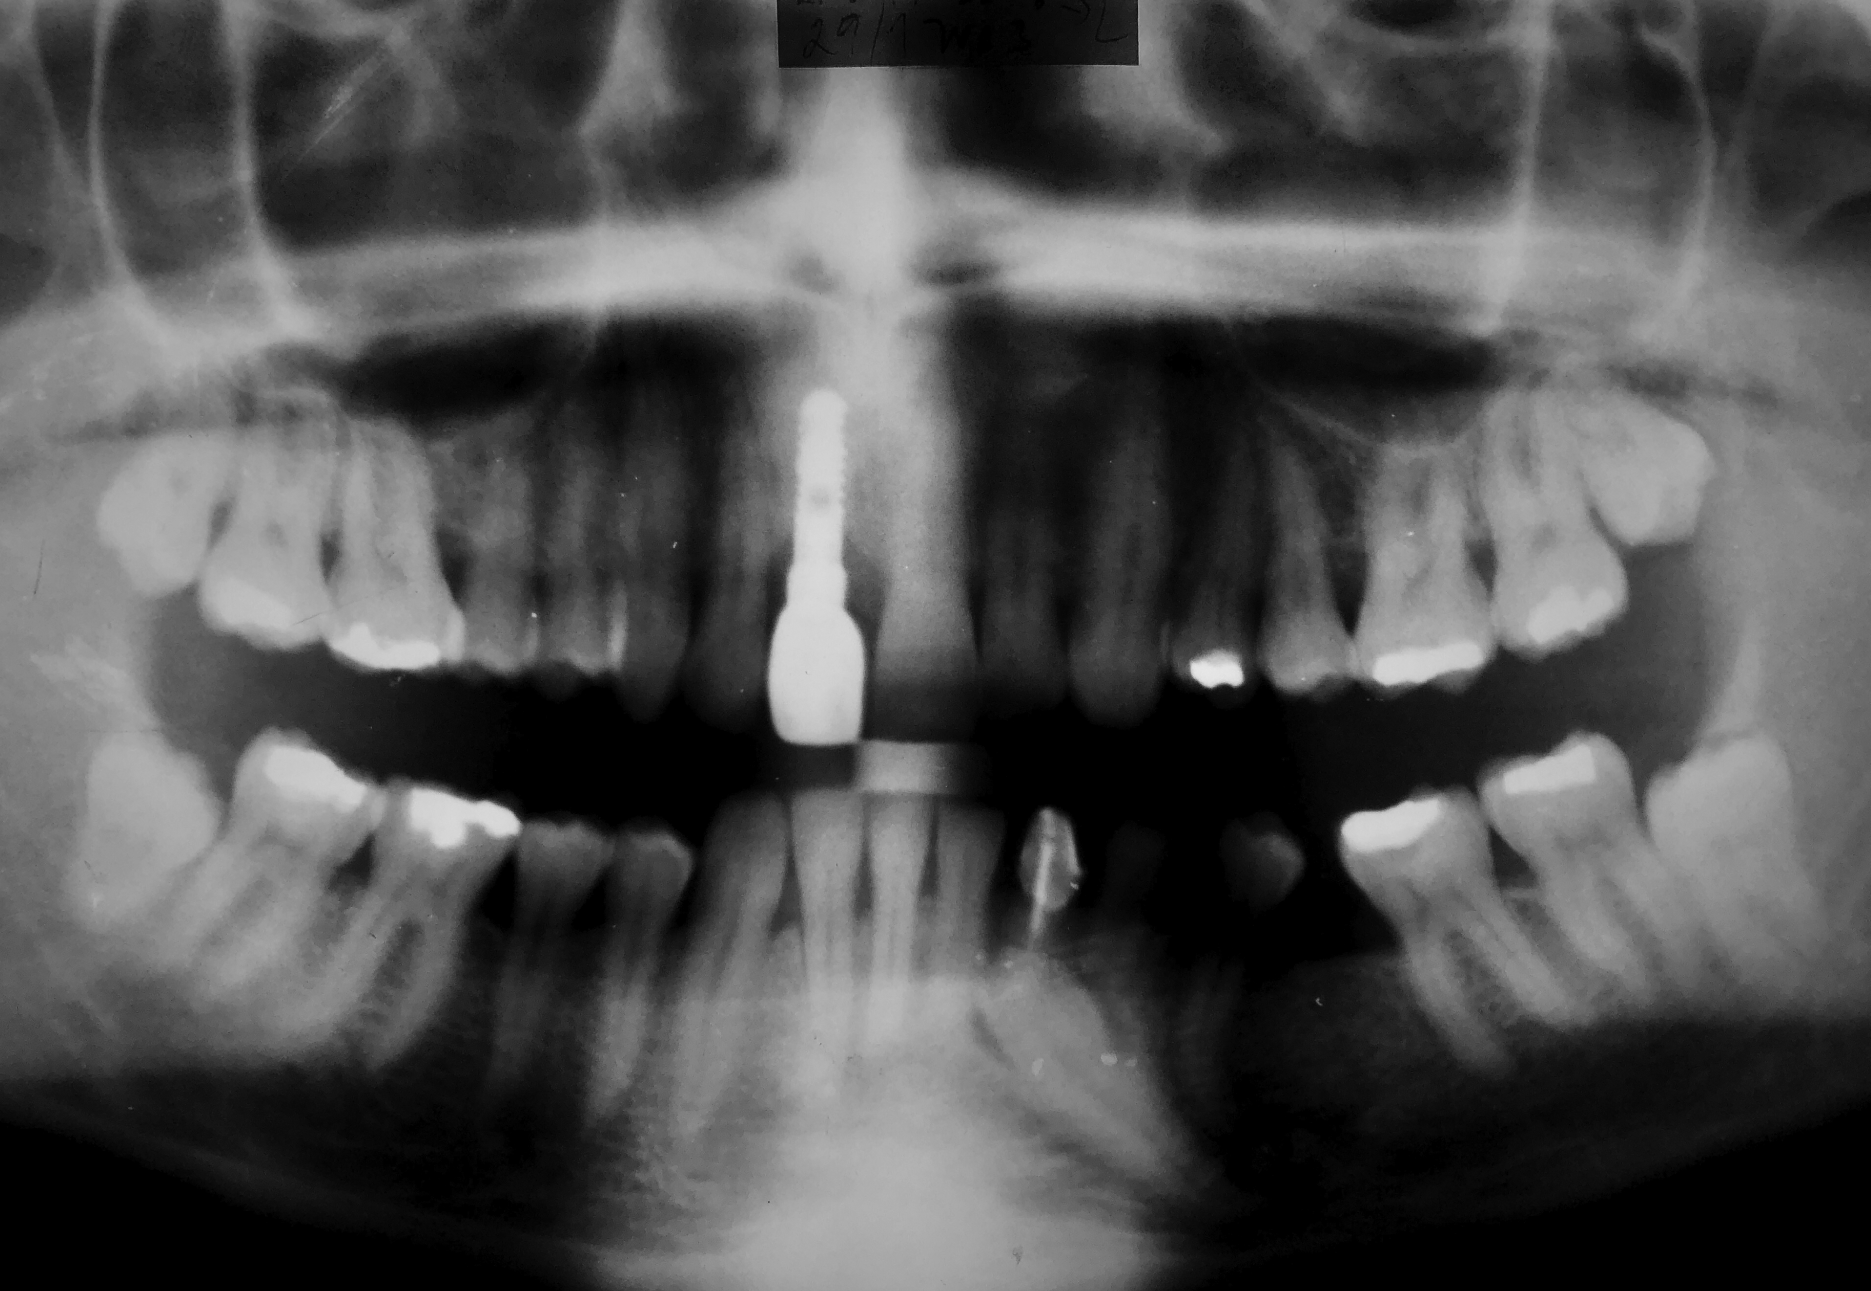

Der Patient stellte sich 14 Tage nach der aufgrund eines Traumas erfolgten Zahnextraktion in Regio 11 mit der Bitte um einen implantatgetragenen Zahnersatz in der Praxis vor. Im März 2001 wurden Änderungen im Bereich der geplanten Implantation festgestellt. Eine Sequestrektomie wurde durchgeführt und die Lücke mit einem abnehmbaren Provisorium behandelt. Die implantologische Behandlung wurde für den Oktober 2001 geplant. Das Implantat IMPLADENT mit dem Durchmesser von 3,7 mm und in der Länge von 12 mm wurde im November 2001 eingesetzt. Nach dem Einheilen des Implantats wurde im Juni 2002 eine metallkeramische Krone aufgesetzt. Der Patient kam zu regelmäßigen Recalls. Weder subjektive noch objektive Änderungen wurden erkannt. Der ursprüngliche Zahnersatz ist auch trotz des signifikanten Bruxismus nach 23 Jahren funktionsfähig und ästhetisch zufriedenstellend.

Ausgangsituation nach der Extraktion des Zahnes 11 infolge eines Traumas. Der Patient möchte den fehlenden Zahn mit einem Implantat ersetzen lassen. Im März 2001 wurden Änderungen im Bereich festgestellt. Eine Sequestrektomie wurde durchgeführt und die Lücke mit einem abnehmbaren Provisorium behandelt.